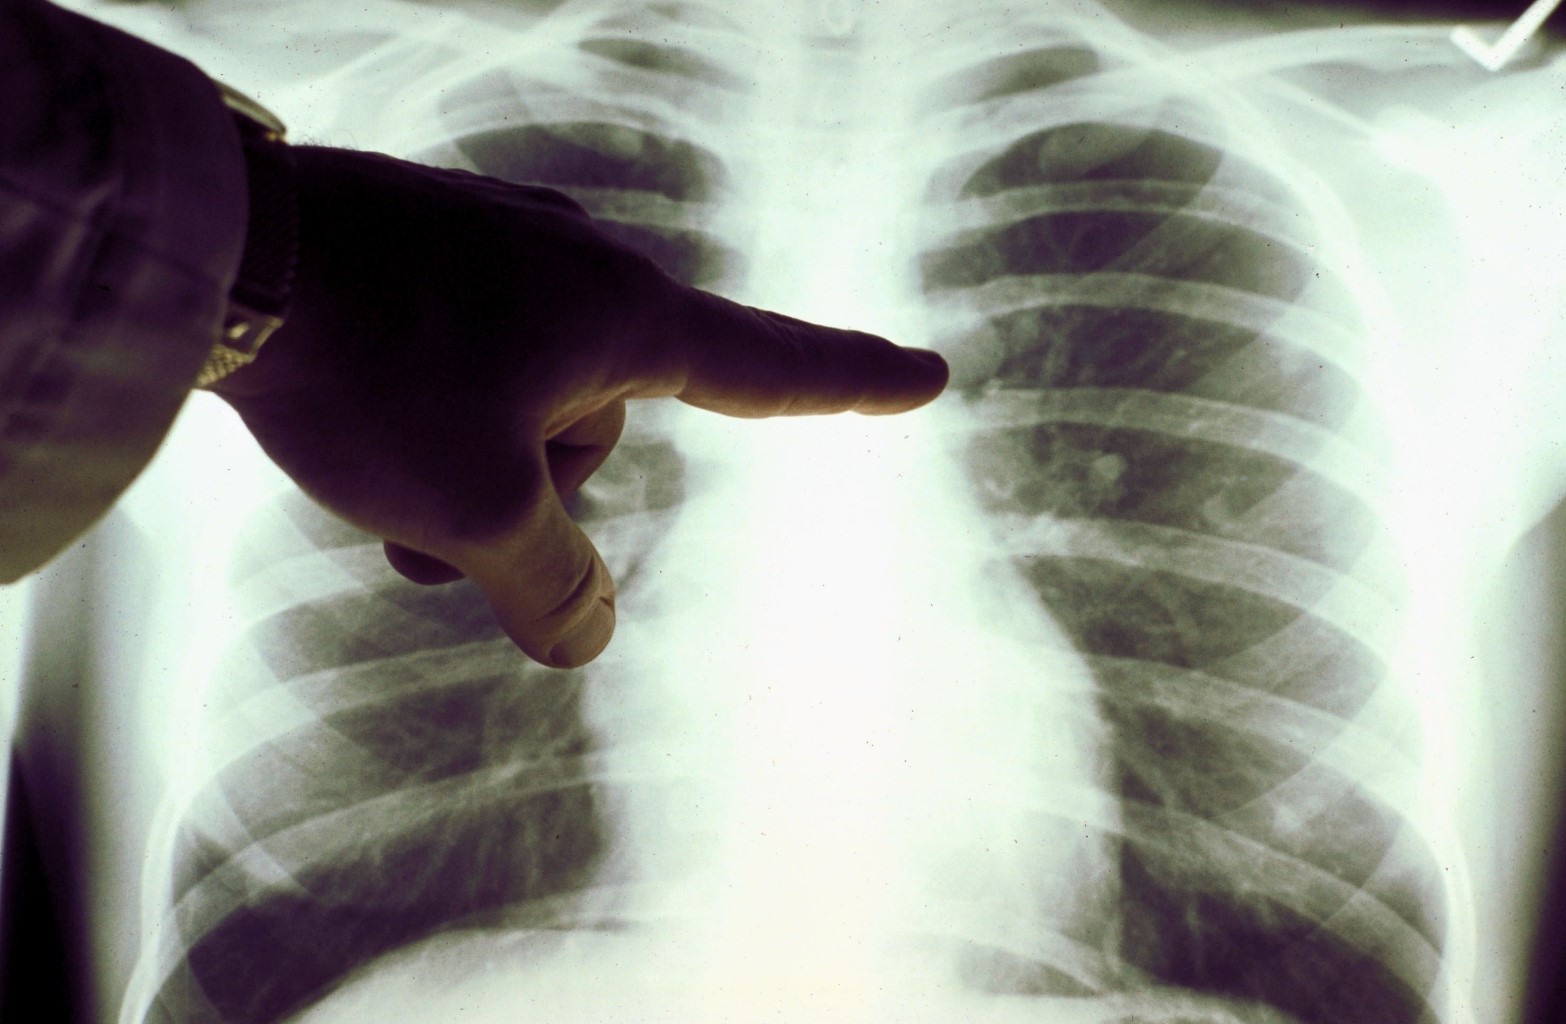

Akciğer filminde siyah alanlar ne kadar fazla ise o kişinin ciğer kapasitesi ve sağlığı o kadar iyi demektir. Beyaz kısımların artması ise akciğerin kapasitesinin azaldığı anlamını taşır.

Karşılaştırılan röntgen sonuçlarıyla Kovid-19’u geçirmiş ve sağlığına kavuşmuş kişilerin ciğerlerinde görülen hasarın sigara bağımlısı olan kişilerden çok daha kötü olduğunu gözler önüne seren Bankhead-Kendall, ‘Sağlıklı bir bireyin röntgen sonucunda siyah alan büyük olur. Bu da o kişinin ciğerlerine alabileceği oksijen seviyesini gösterir.

Bankhead-Kendall, karşılaştırma yapabilmek için sağlıklı bir bireye ait olan akciğer filmini de paylaştı. Kovid-19’u atlatan kişilerin nefes almakta sıkıntı yaşayabileceğine vurgulayan Bankhead-Kendall, sosyal medya hesabından, ‘Bunu kimin duyması gerek bilmiyorum fakat koronavirüsü geçirmiş bir kişinin akciğerleri, yıllarca sigara içmiş bir tiryakinin ciğerlerinden çok ama çok kötü. Bu insanlar bayılıyor, nefesleri kesiliyor ve benzeri birçok sorun yaşıyorlar’ dedi.